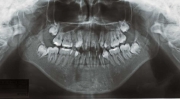

治療後2年経過時